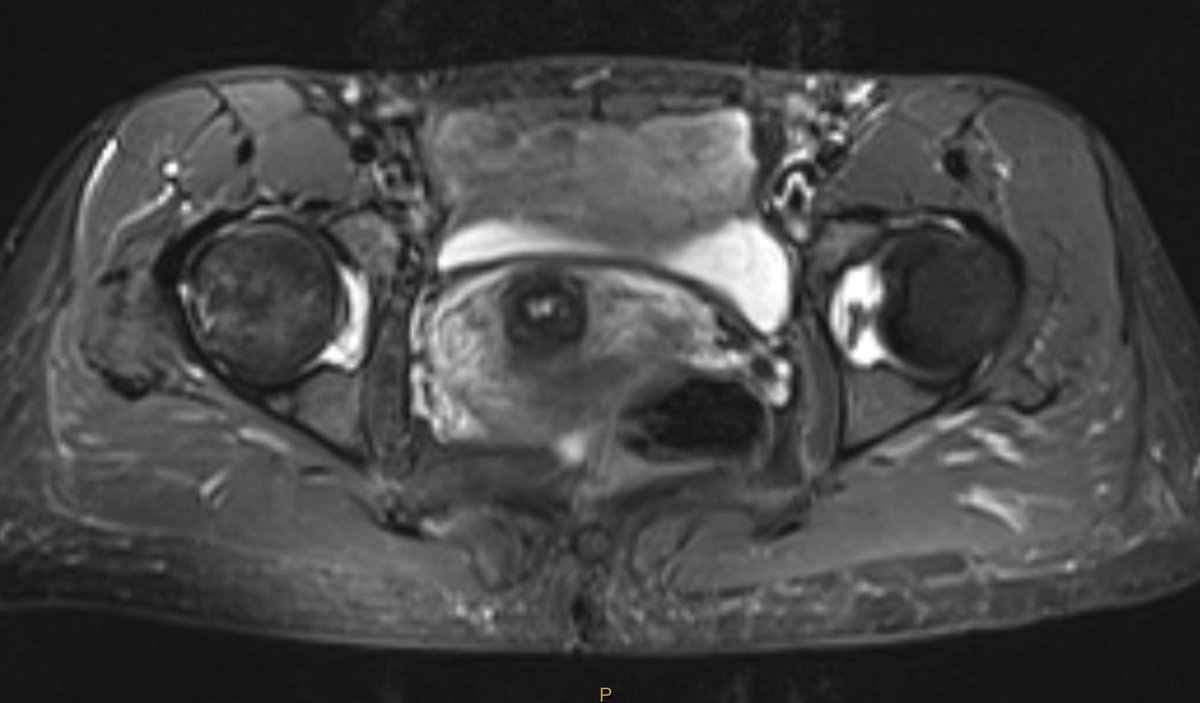

#CaseOfTheWeek‼️🥳‼️ ☢️🩻☠️Case#22☠️🩻☢️ #Mass 📲➡️➡️#Diagnosis❔❓❔ #FOAMRad #RadEd #MedEd #OrthoEd #OrthoTwitter @ssr_rwg @UWRadRes @ISSVA_org